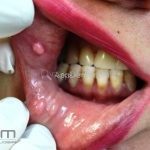

Doença de Heck (hiperplasia epitelial focal)

A doença caracteriza-se por múltiplas pápulas ou nódulos planos, normocrômicos, encontrados na mucosa gengival, labial ou bucal.

As lesões são assintomáticas e não possuem risco de transformação maligna.